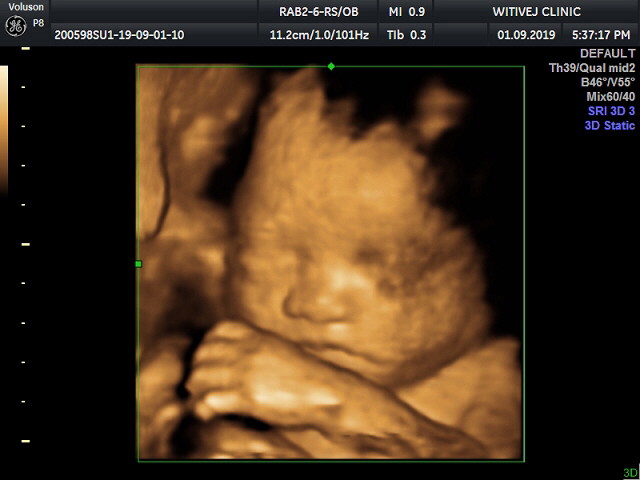

29 weeks!